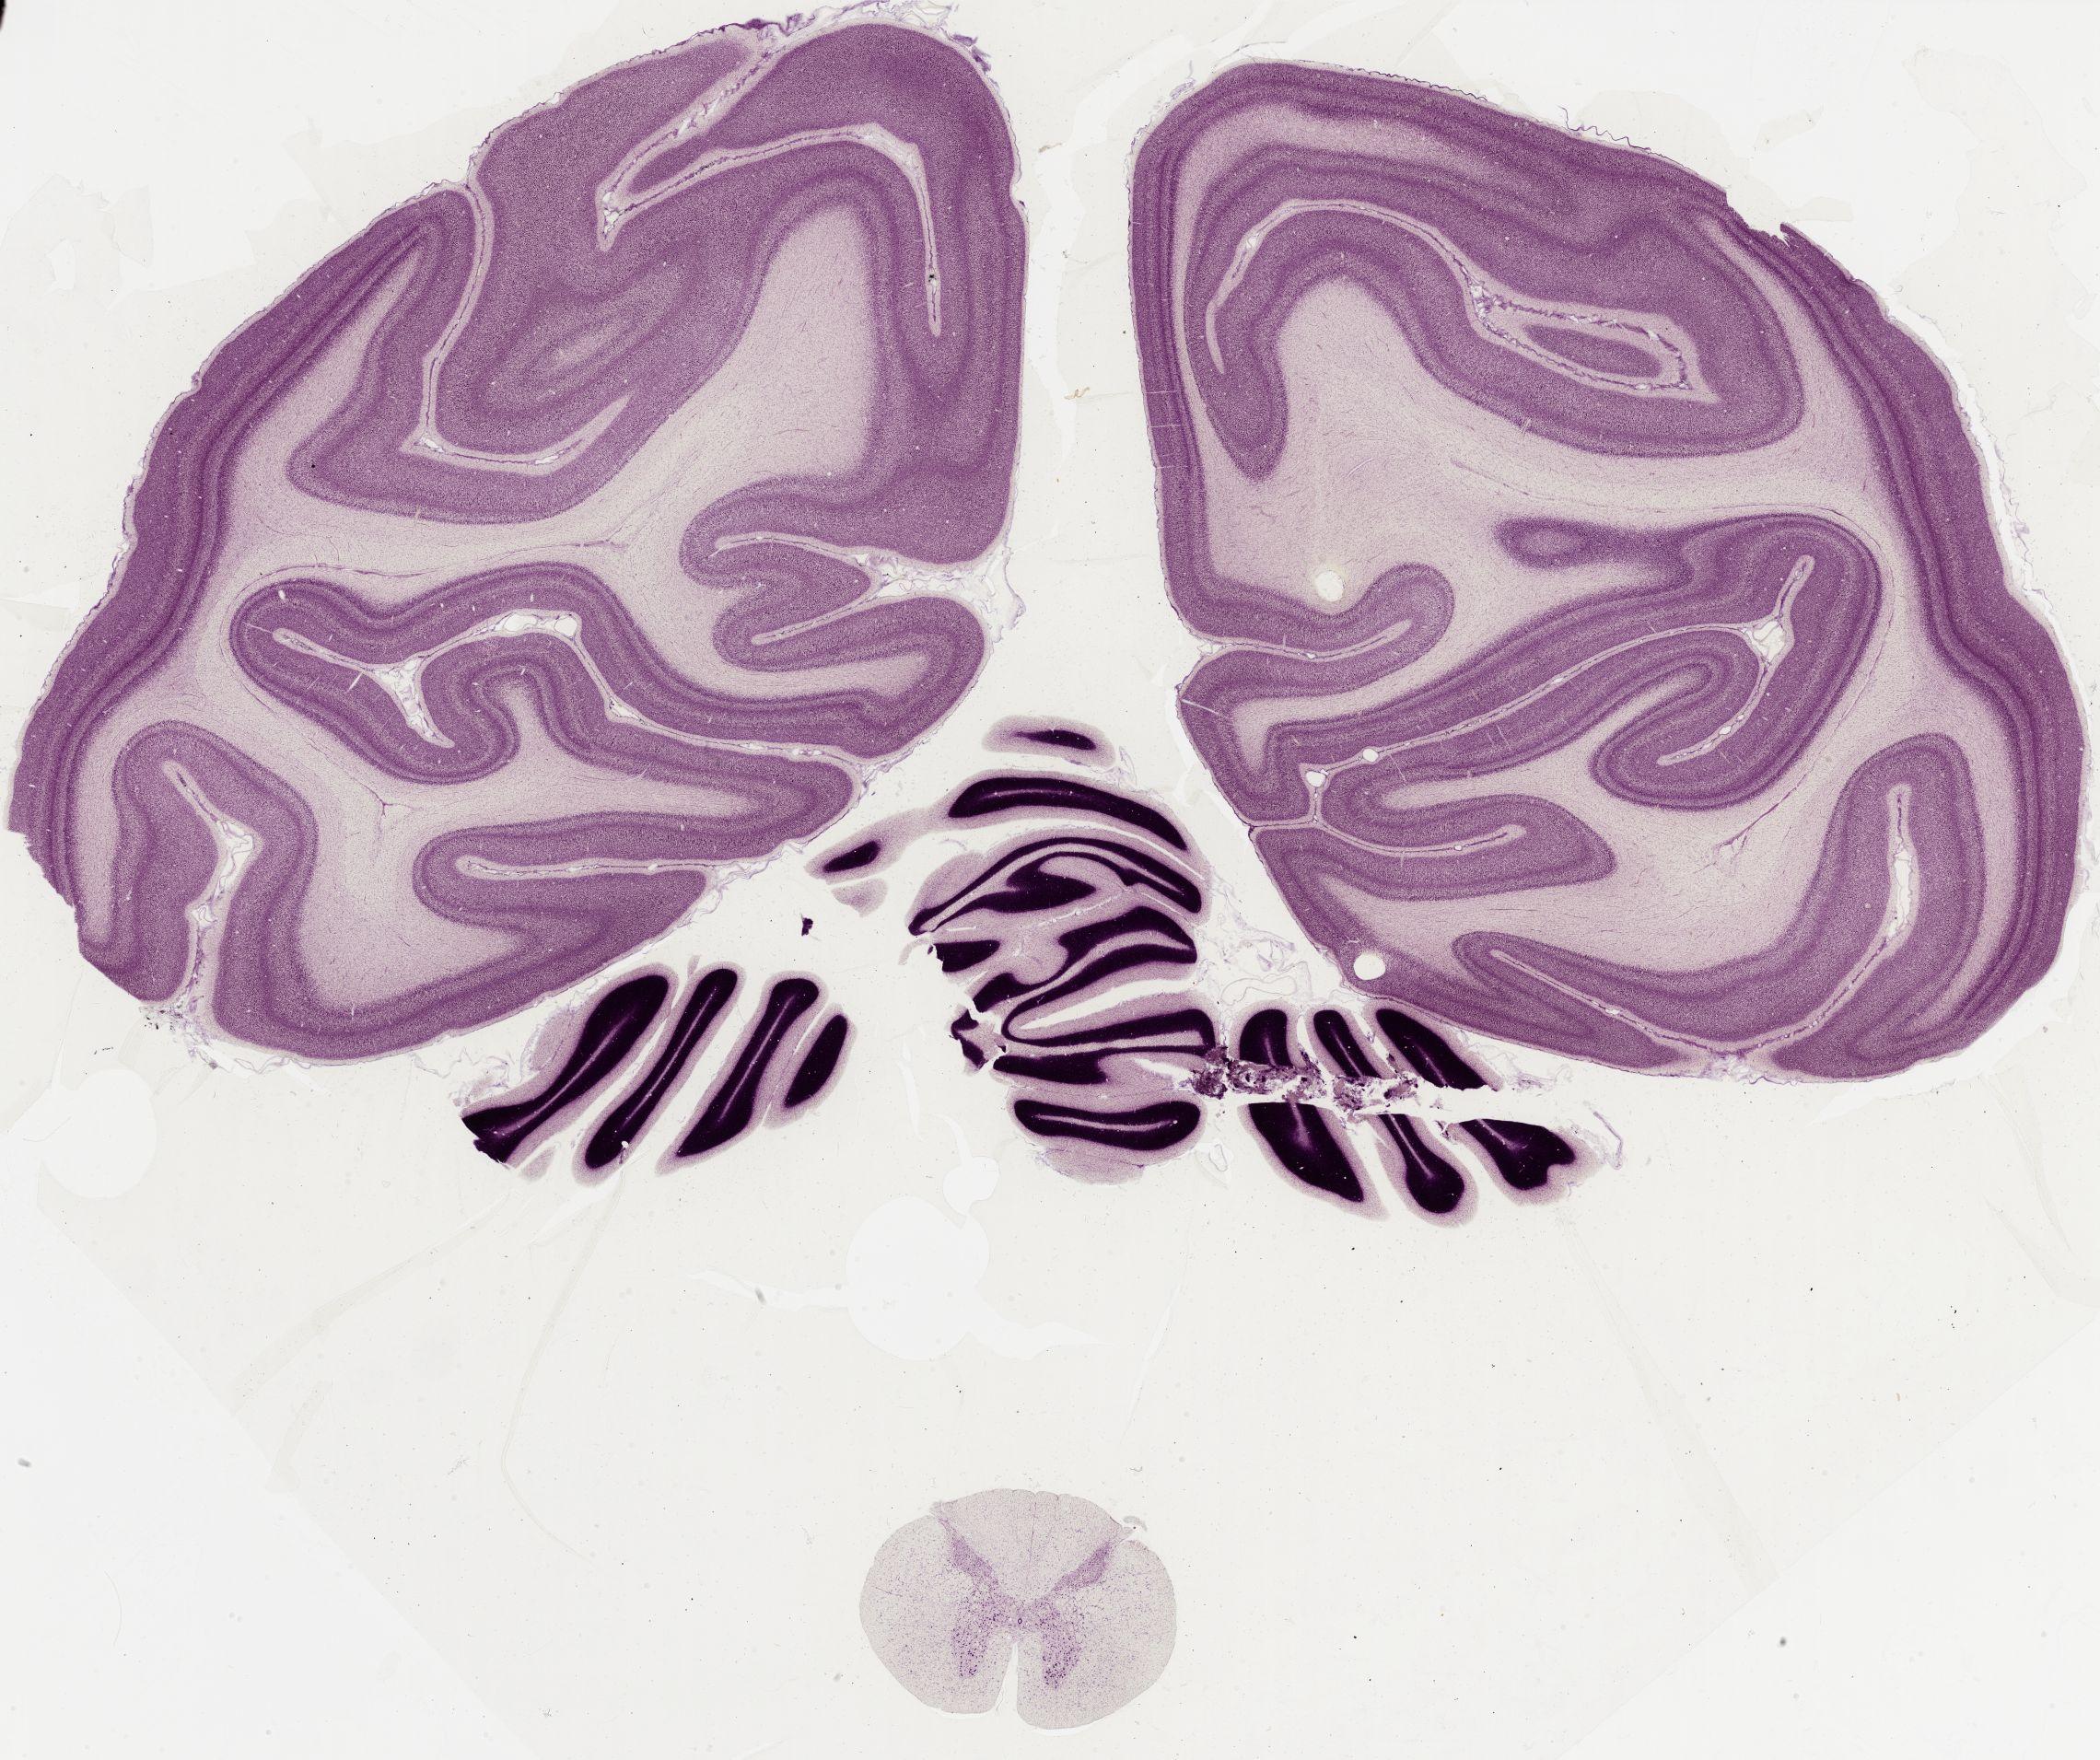

Datasets -> Macaca Mulatta -> Nissl, coronal, histo, Whole-Brain, adult

[ Metadata ]   ·   Source: Edward G. Jones

Displaying Sections 41 thru 56 of 56 Sections for this Dataset

0565 - labeled